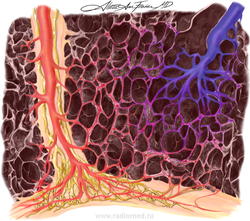

Легочный капиллярный гемангиоматоз